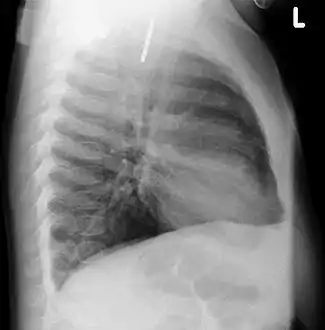

A coin seen on AP CXR in the esophagus

A coin seen on lateral CXR in the esophagus